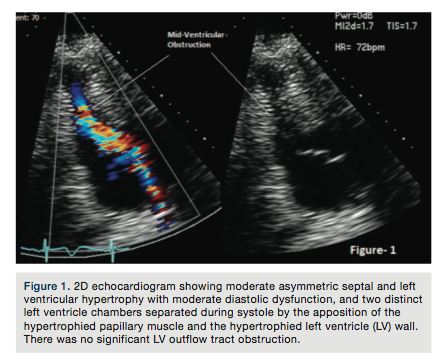

On physical exam, 3/6 harsh crescendo-decrescendo systolic murmur was heard on the left lower sternal border. Physical exam of the head and neck showed hypertelorism, low-set posteriorly rotated ears, downward eye slants, and webbed neck. A 12-lead ECG showed sinus rhythm at 98 beats per minute and left axis deviation with ST-segment depression in lateral chest leads, concerning for possible lateral ischemia or infarct. Three sets of troponin (I) were checked sequentially with 6-hour intervals and the results were (0.03), (12.50), (11.33); normally (<0.01). The patient was managed as a non-ST-segment elevation myocardial infarction (NSTEMI). Subsequent 2D echocardiogram showed moderate asymmetric septal and left ventricular

hypertrophy with moderate diastolic dysfunction, and two distinct left ventricle chambers separated during systole by the apposition of the hypertrophied papillary muscle and the hypertrophied left ventricle (LV) wall (Figure 1). There was no significant LV outflow tract obstruction.